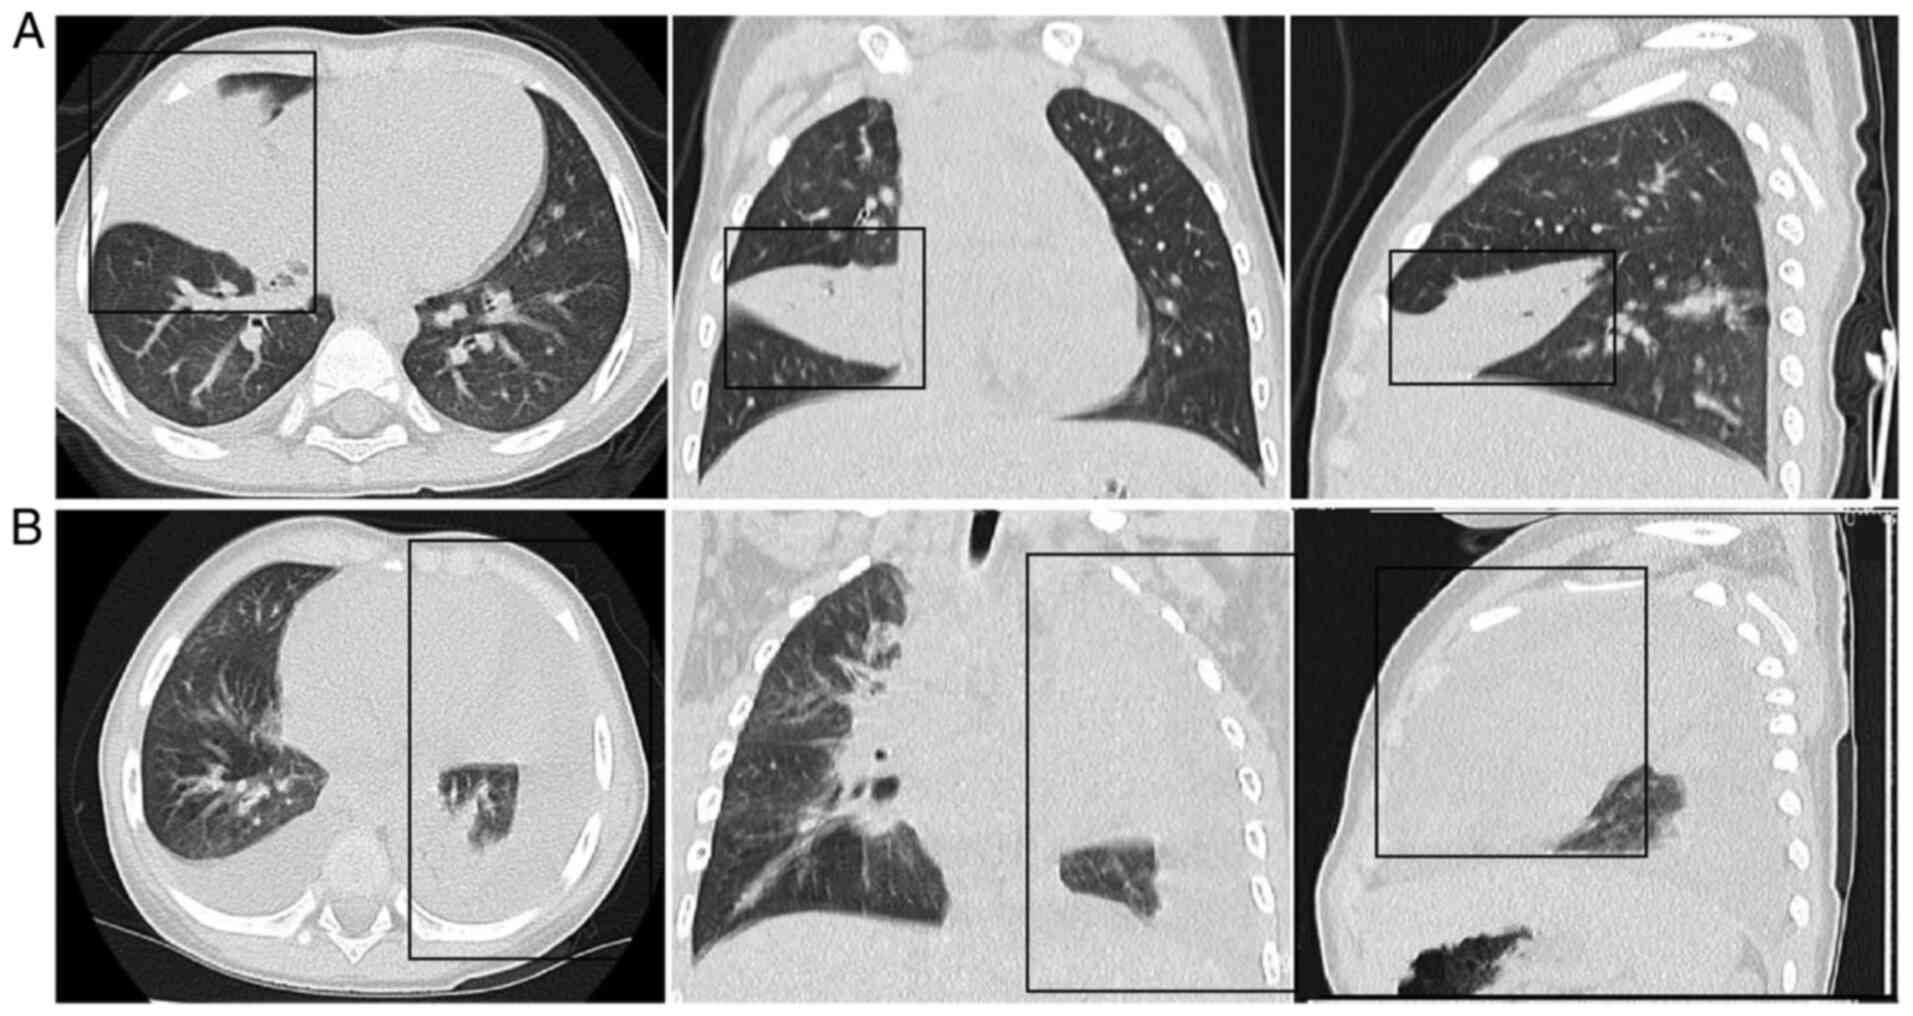

Patients with MPP displayed typical MPP clinical symptoms and were diagnosed with pneumonia. The M. pneumoniae IgM antibody in the serum and M. pneumoniae DNA detected via PCR from throat swabs showed positive results. The clinical characteristics of the cases are listed in Tables SI and SII. Abnormal findings on chest radiographs were observed in all patients with MPP. The chest scans primarily revealed diffuse infiltration of both lungs in NRMPP cases. However, RMPP cases exhibited unequivocal focal or segmental consolidation (Fig. 1A) with pleural effusion (Fig. 1B).